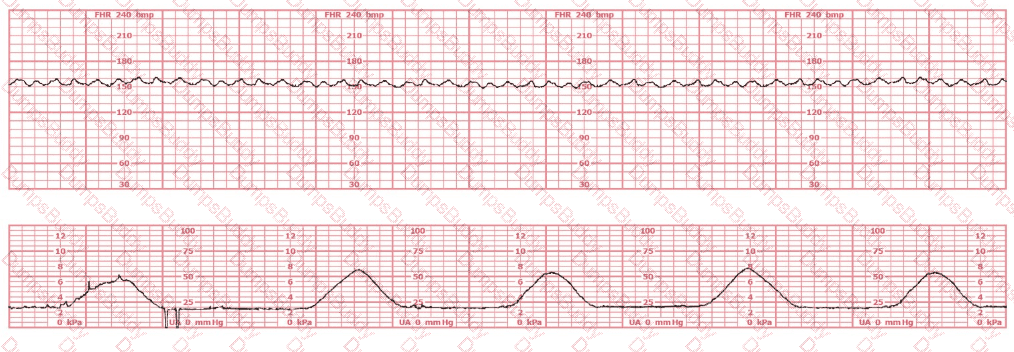

A woman (G1P0) arrives in triage with a pain score of 4/10 at 39-weeks gestation. The fetal heart rate tracing shown is obtained. The best intervention is to: